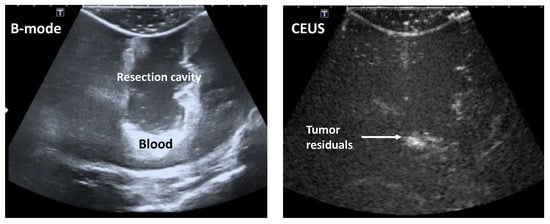

However, the identification of tumor residuals in the iUS data remains in general complex for the expert-eye. Depending on the position of the tumor within the patient’s head, the resection cavity, as well as other cerebral structures like blood vessels, potentially ventricles and bone structures, are usually well depicted in the iB-mode image data. However, the possible tumor residuals are hardly differentiable from other hyperechogenic structures, like the border of the resection cavity, blood or artifacts (Figure 2, left). Furthermore, it is only attempted to enhance the blood vessels and vascularized structures, like tumors, in the iCEUS image data. Furthermore, the borders of the resection cavity, which are important structures that are needed to analyze the images correctly, are hardly or not at all visible (Figure 2, right). The combination of the information in the iB-mode and iCEUS image data, also called data fusion, can support the identification of tumor residuals.

Figure 2.

Intraoperative B-mode ultrasound (iB-mode) (left) and iCEUS (contrast enhanced ultrasound (CEUS)) (right) patient image data acquired at the end of a brain tumor operation.